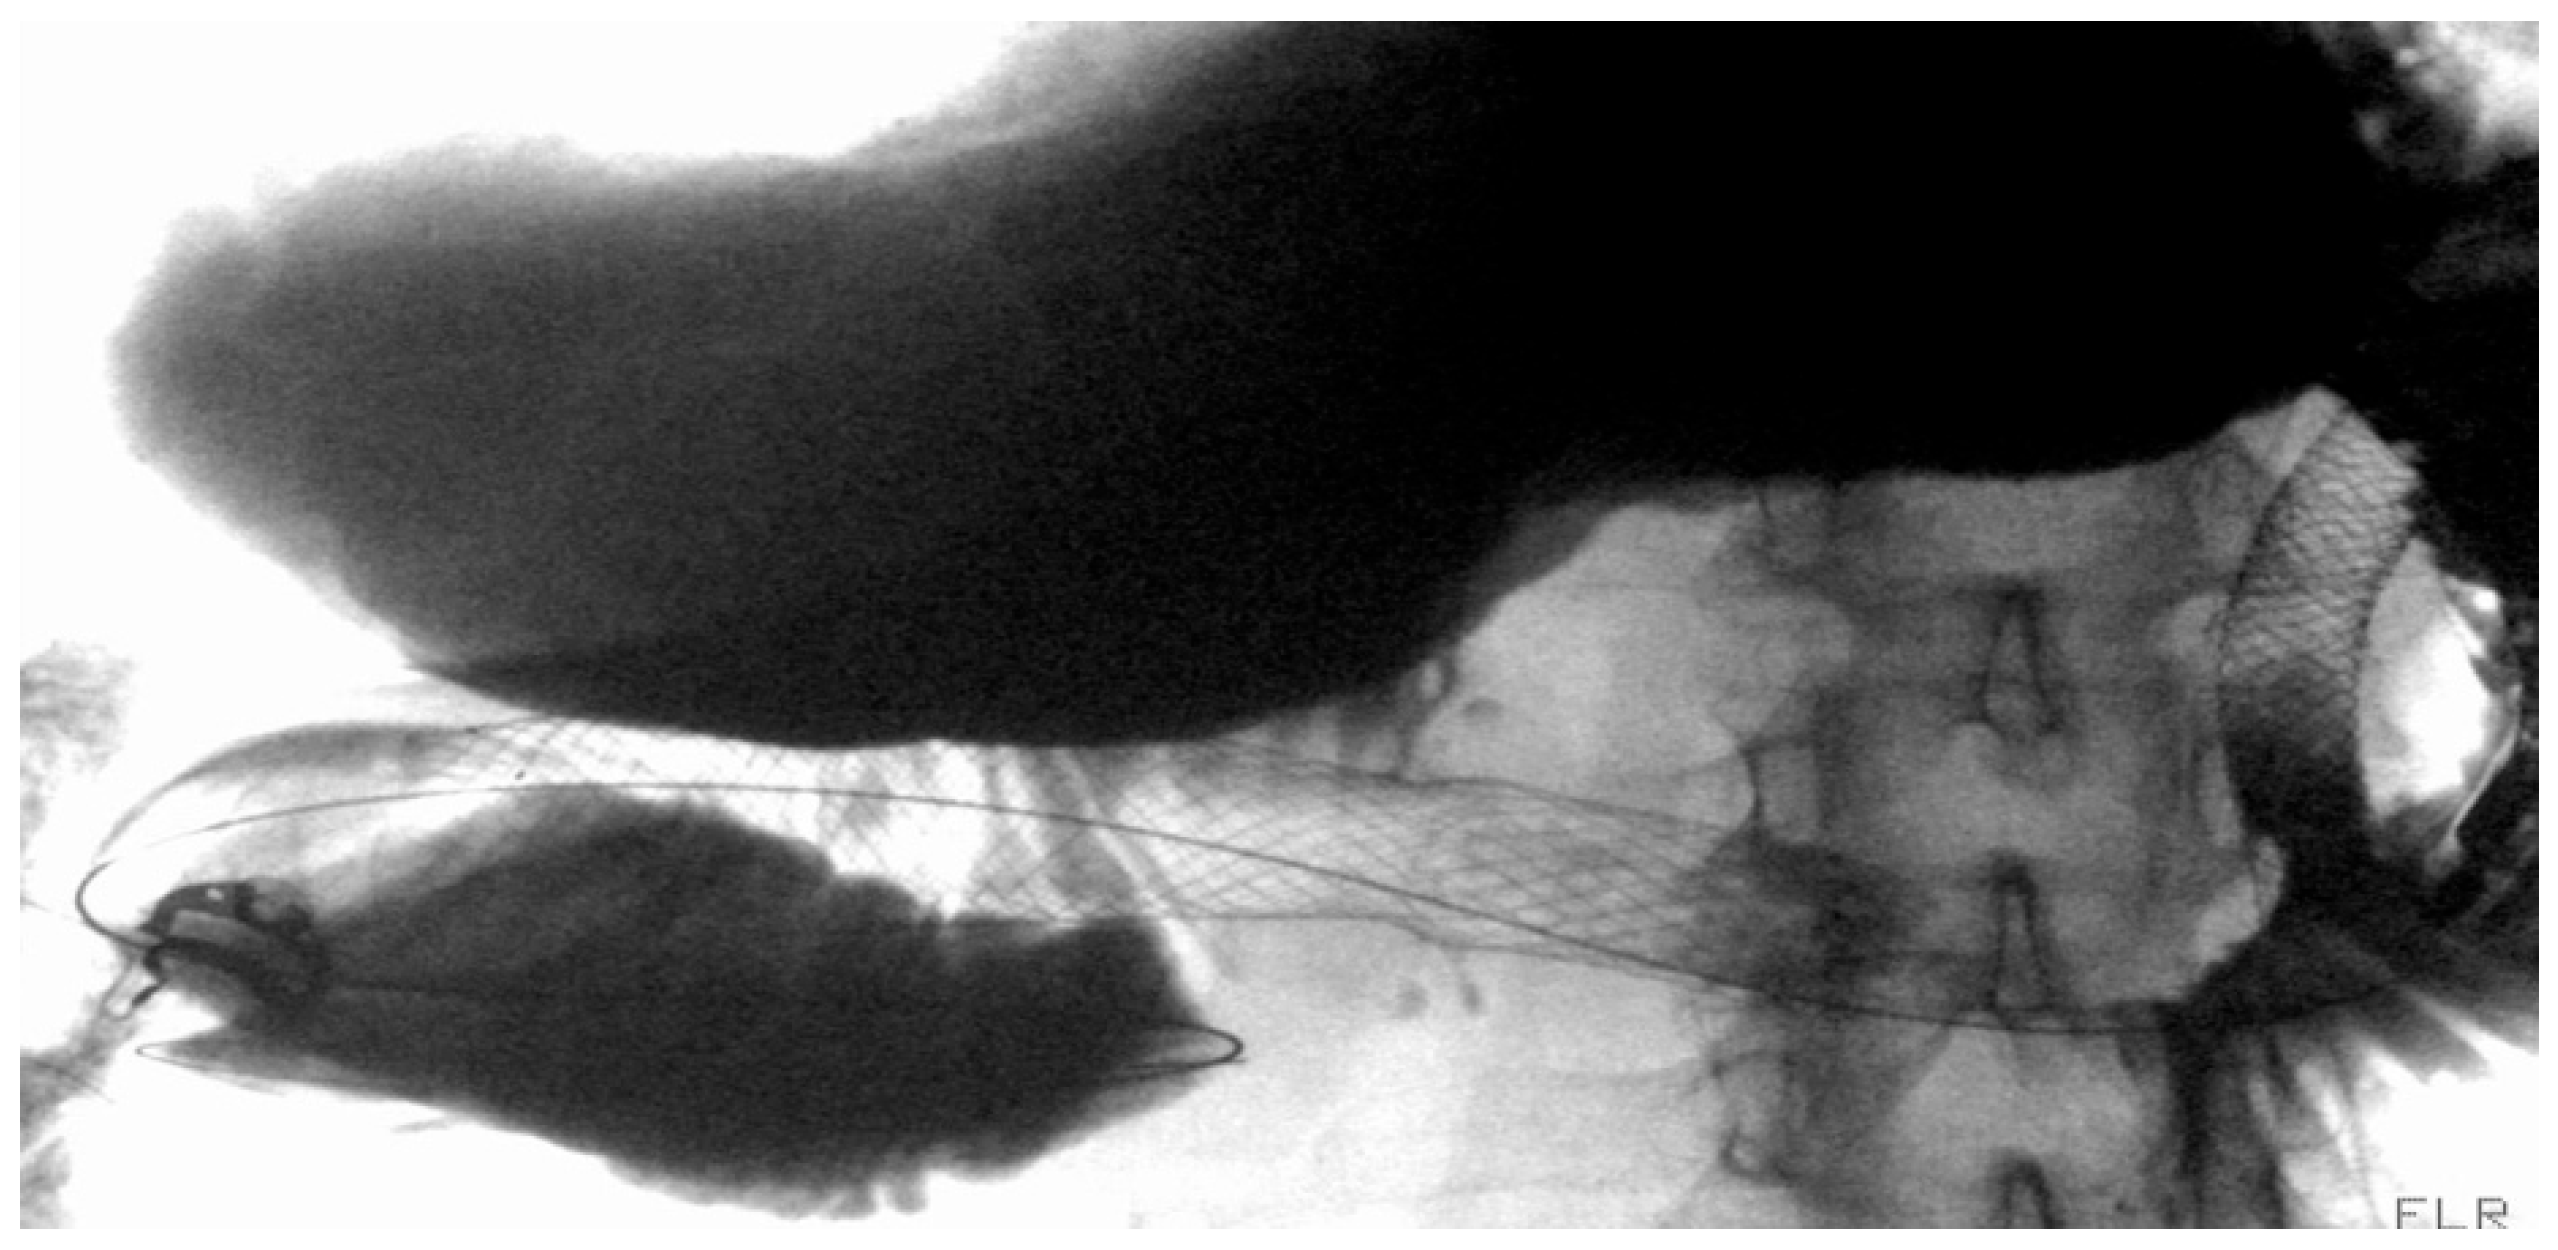

4.1.2. LAMS

Indication and Mechanism of Action

- Direct technique: puncture of the jejunal loop with a 19G needle and contrast injection to confirm position [126].

- Device-assisted EUS-GE: balloon or enteroscope passed across the stenosis to aid EUS visualization and targeting [127].

- Wireless Endoscopic Simplified Technique (WEST): described by Bronswijk et al. in 2020 and currently the most widely used technique [128], this approach involves jejunal distension via a nasoenteric tube with saline and dye, followed by “free-hand” single-step LAMS deployment under EUS guidance [128].